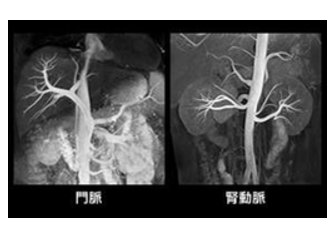

• 磁気共鳴コンピューター断層装置は放射線を使わず、巨大な磁石を使用する被爆のない安全な装置です。X線を使用しないため無侵襲または低侵襲で、患者さんに優しい安全な検査が行えます。 CTによる血管検査では、造影剤の使用が不可欠でしたが、1.5テスラMRI検査では、造影剤を不使用または最小限の造影剤で大きな血管に関する撮影が容易に可能です。 (MRAとは…Magnetic Resonance Angiographyの略で、MRIを利用して血管像を描出する方法です) また従来のMRIより短時間で撮影が可能となっています。